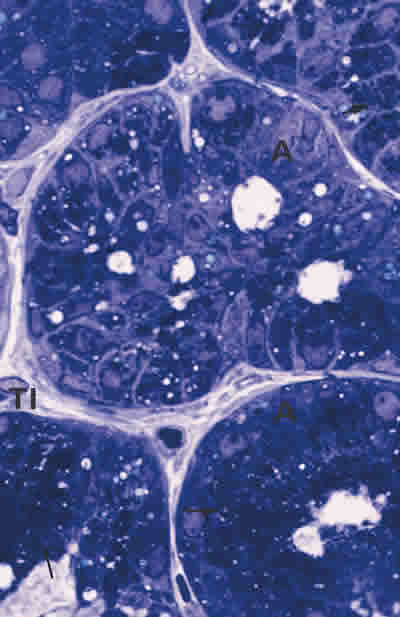

Figura 14

BIOPSIA EN UNA PERSONA CONTROL. LA GLÁNDULA LAGRIMAL PRINCIPAL PRESENTA ACINOS (A) CONSTITUIDOS POR CÉLULAS UNIDAS CON ABUNDANTE NÚMERO DE GRÁNULOS DE SECRECIÓN (FLECHA ARRIBA). EL TEJIDO CONECTIVO INTERSTICIAL (TI) ES ESTRECHO, LAXO Y CON POCAS CÉLULAS. TINCIÓN AZULES DE RICHARDSON. MAGNIFICACIÓN ORIGINAL X100.